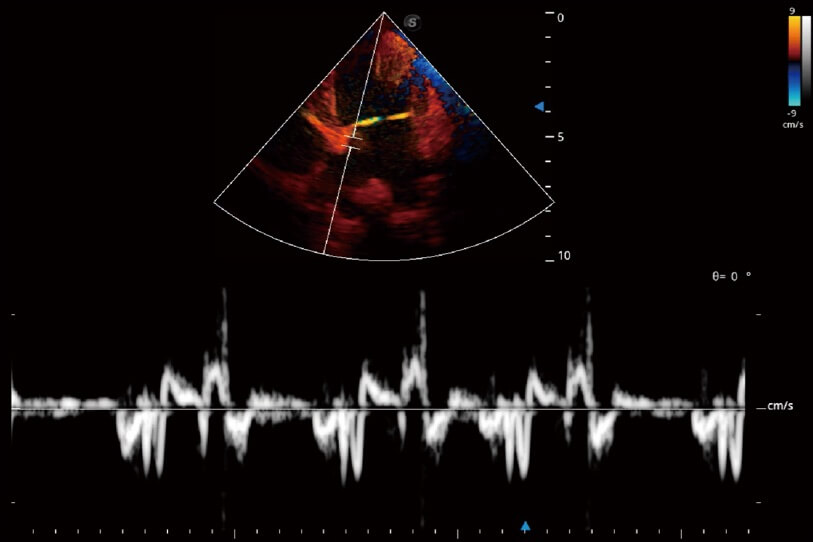

實(shí)時(shí)用顏色表示心肌組織運(yùn)動,觀察和定量組織的運(yùn)動情況,對快速檢測與評估心肌的灌注和活性、電傳導(dǎo)及心肌收縮和舒張功能等均能提供重要的診斷信息。